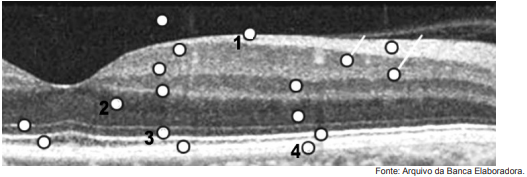

Observe o exame abaixo.

Com relação a esse exame, é correto afirmar que o número